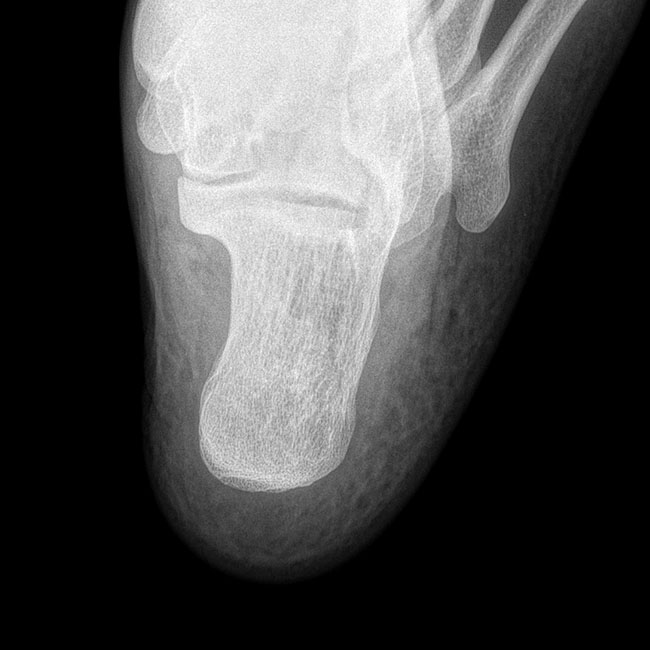

臨床樣本